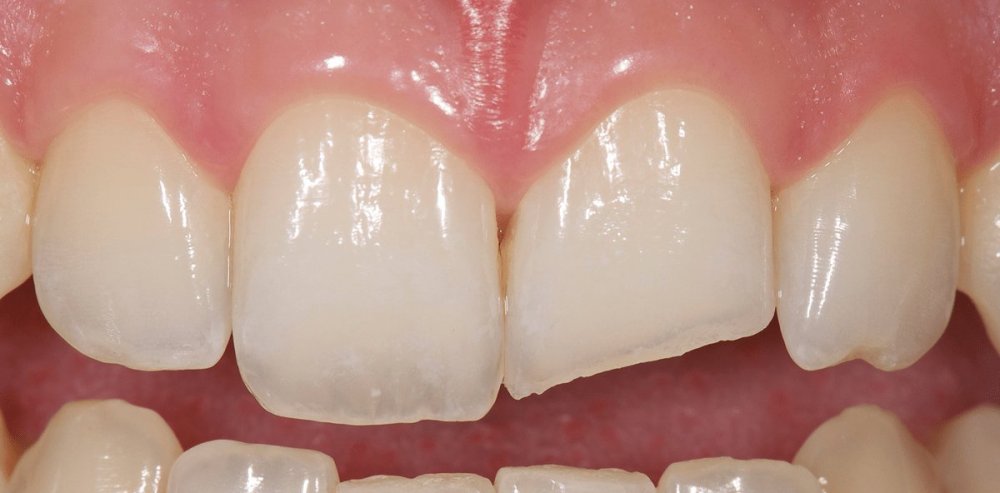

Daimi dişlərin travmatik zədələnmələri uşaq və yeniyetməlik dövründə olan şəxslərdə çox tez-tez rast gəlinir. Tac qırılmaları və lüksasiya travmalar içərisində ən çox rast gəlinənlərdir. Ancaq müxtəlif kliniki hallarda digər zədələnmə formaları da aşkar edilə bilir.

Bu tip zədələnmələrin bu sahədə təcrübəsi olan yüksək ixtisaslı həkim tərəfindən həyata keçirilməsi olduqca önəmlidir. Əks təqdirdə yalnış müalicə dişlərin erkən itirilməsinə səbəb ola bilir. Doğru yanaşma ilə isə ciddi zədələnmələrdən sonra belə zədələnmiş dişləri bəzən müəyyən bir müddətə bəzən isə həmişəlik bərpa etmək mümkün olur.